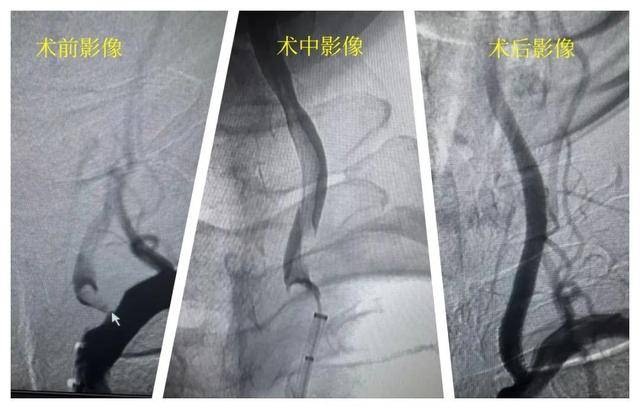

医院卒中团队迅速响应,启动绿色通道。在张先生入院后的90分钟“黄金时间窗”内,神经内科一病区副主任、副主任医师王家祺成功为其实施了微创动脉取栓手术,将堵塞血管的血栓精准取出,迅速恢复了脑部血供。术后一周复查时,张先生已能够独立行走,语言功能也得到了明显改善。

王家祺表示,张先生的快速康复,很大程度归功于及时送医、精准诊断和在黄金时间窗内完成的取栓手术,再次凸显了“时间就是大脑”对于急性脑梗(中风)患者的重要性。